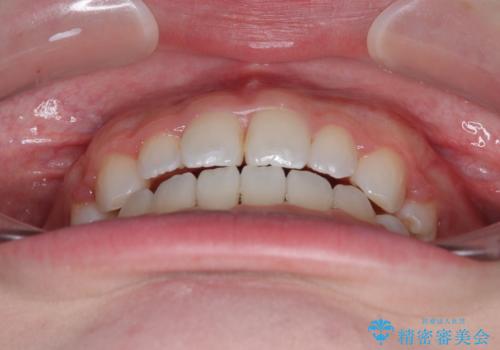

当初は舌のトレーニングをしっかりと行ってくださったおかげで、短い期間で治療を終えることができました。

- 前歯が開いて飛び出していることを気にして来院された患者様です。

舌の突出癖により上下前歯は接触できず、更には前方に押し出されて出っ歯になっている状態でした。